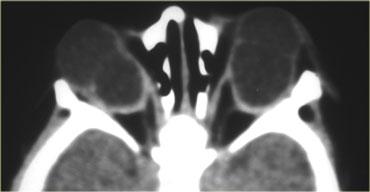

Hình bên trái là hình ảnh CT của một bệnh nhân bị chấn thương mắt trái.

Hãy phân tích hình ảnh để tìm 5 dấu hiệu trước khi tiếp tục đọc.

Các dấu hiệu bao gồm:

- Tiền phòng nông hơn so với bên phải, gợi ý vỡ nhãn cầu.

- Tỷ trọng trong tiền phòng tăng, gợi ý xuất huyết tiền phòng (hyphema).

- Tỷ trọng của thủy tinh thể giảm, cho thấy bệnh nhân bị đục thủy tinh thể do chấn thương.

- Có vùng tăng tỷ trọng trong buồng dịch kính, gợi ý xuất huyết dịch kính.

- Nhãn cầu dẹt ở mặt sau, cho thấy có vỡ dịch kính kèm theo.

Vỡ nhãn cầu thường gặp nhất ở vị trí tiền phòng.